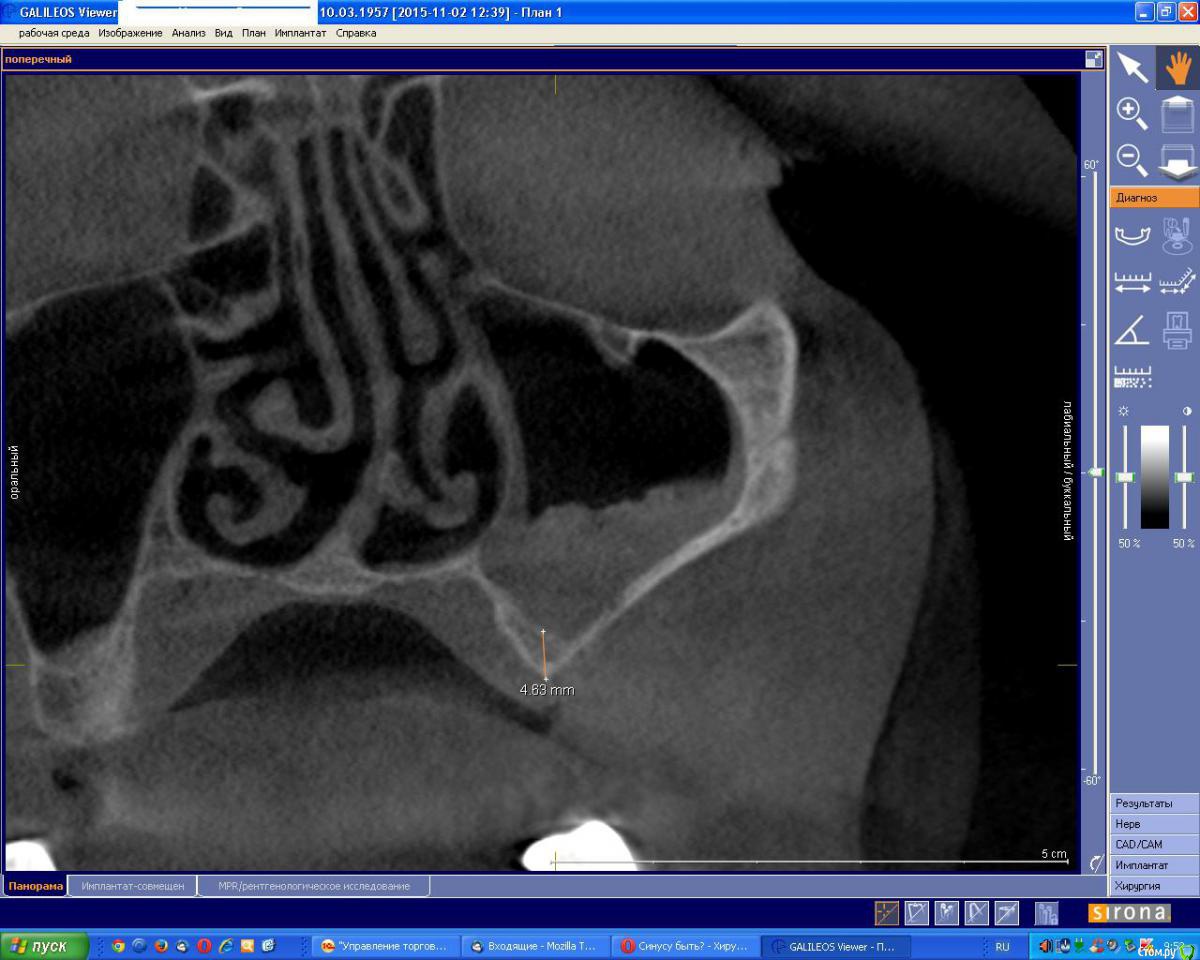

an_ver Опубликовано 2 ноября, 2015 Поделиться Опубликовано 2 ноября, 2015 Вот такое КТ..думаю делать нельзя.Ваше мнение коллеги? Ссылка на комментарий

an_ver Опубликовано 2 ноября, 2015 Автор Поделиться Опубликовано 2 ноября, 2015 (изменено) Соустье закрыто..или еле открыто...и чет гипертрофия слизистой не нравиться.А сосудик в стенке светит)) Изменено 2 ноября, 2015 пользователем an_ver Ссылка на комментарий

an_ver Опубликовано 3 ноября, 2015 Автор Поделиться Опубликовано 3 ноября, 2015 А по моему тут синусу быть....закрытому! Ты же владеешь "сакральными" знаниями...Как предполагаешь отстучаться сакрально при такой высоте и форме гребня? Ссылка на комментарий

an_ver Опубликовано 3 ноября, 2015 Автор Поделиться Опубликовано 3 ноября, 2015 Полагаешь при такой форме не "простучать"?Слишком тонко и гребень острый и тонкий..такое уже было но толще дно было...я тем же остеотомом немного гребень плющил))...думаю не зацепится в такой толщине Ссылка на комментарий

gum Опубликовано 5 ноября, 2015 Поделиться Опубликовано 5 ноября, 2015 Можно уточнить почему на открытый синус не решаетесь, если хотите сделать закрытый. Риски мне кажется примерно одинаковы. Сосуд светит, но окно можно пониже или я ошибаюсь? 1 Ссылка на комментарий

an_ver Опубликовано 5 ноября, 2015 Автор Поделиться Опубликовано 5 ноября, 2015 Можно уточнить почему на открытый синус не решаетесь, если хотите сделать закрытый. Риски мне кажется примерно одинаковы. Сосуд светит, но окно можно пониже или я ошибаюсь?Я и не собирался закрытым)) почему так решили? Сосуд мелкого диаметра не проблема.Сегодня сделаю.Получится,отфотаю Ссылка на комментарий